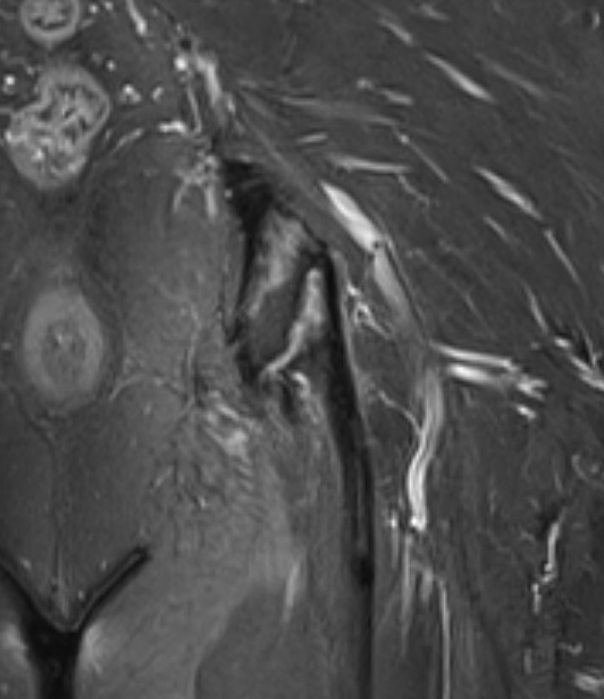

MRI

Peritendinous edema / low grade partial tears / tendinopathy

High grade partial tears

- identify high grade partial tear

- peel off

- debride and repair

Elevate high grade tear with Cobb, exposing bare ischial tuberosity (*)